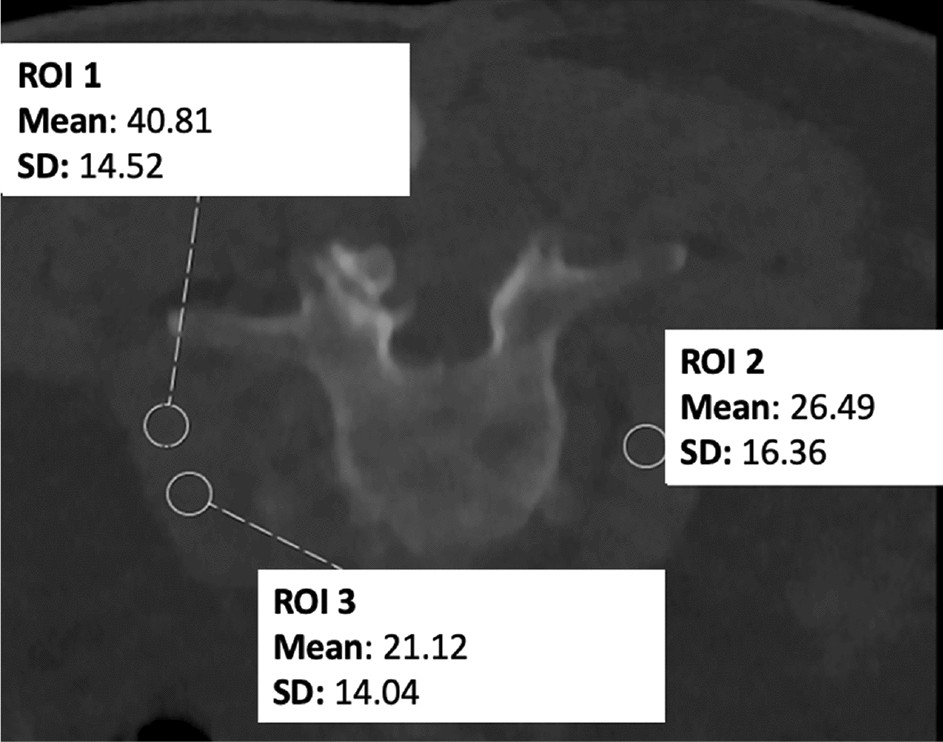

Figure 3

Measurement of image noise for a planned lumbosacral biopsy. Three measurements within the psoas muscle were performed to derive attenuation values from manually placed circular regions of interest (ROIs).